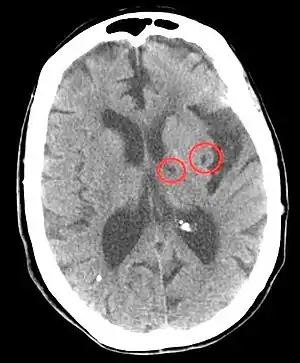

CT scan of two lacunar strokes.